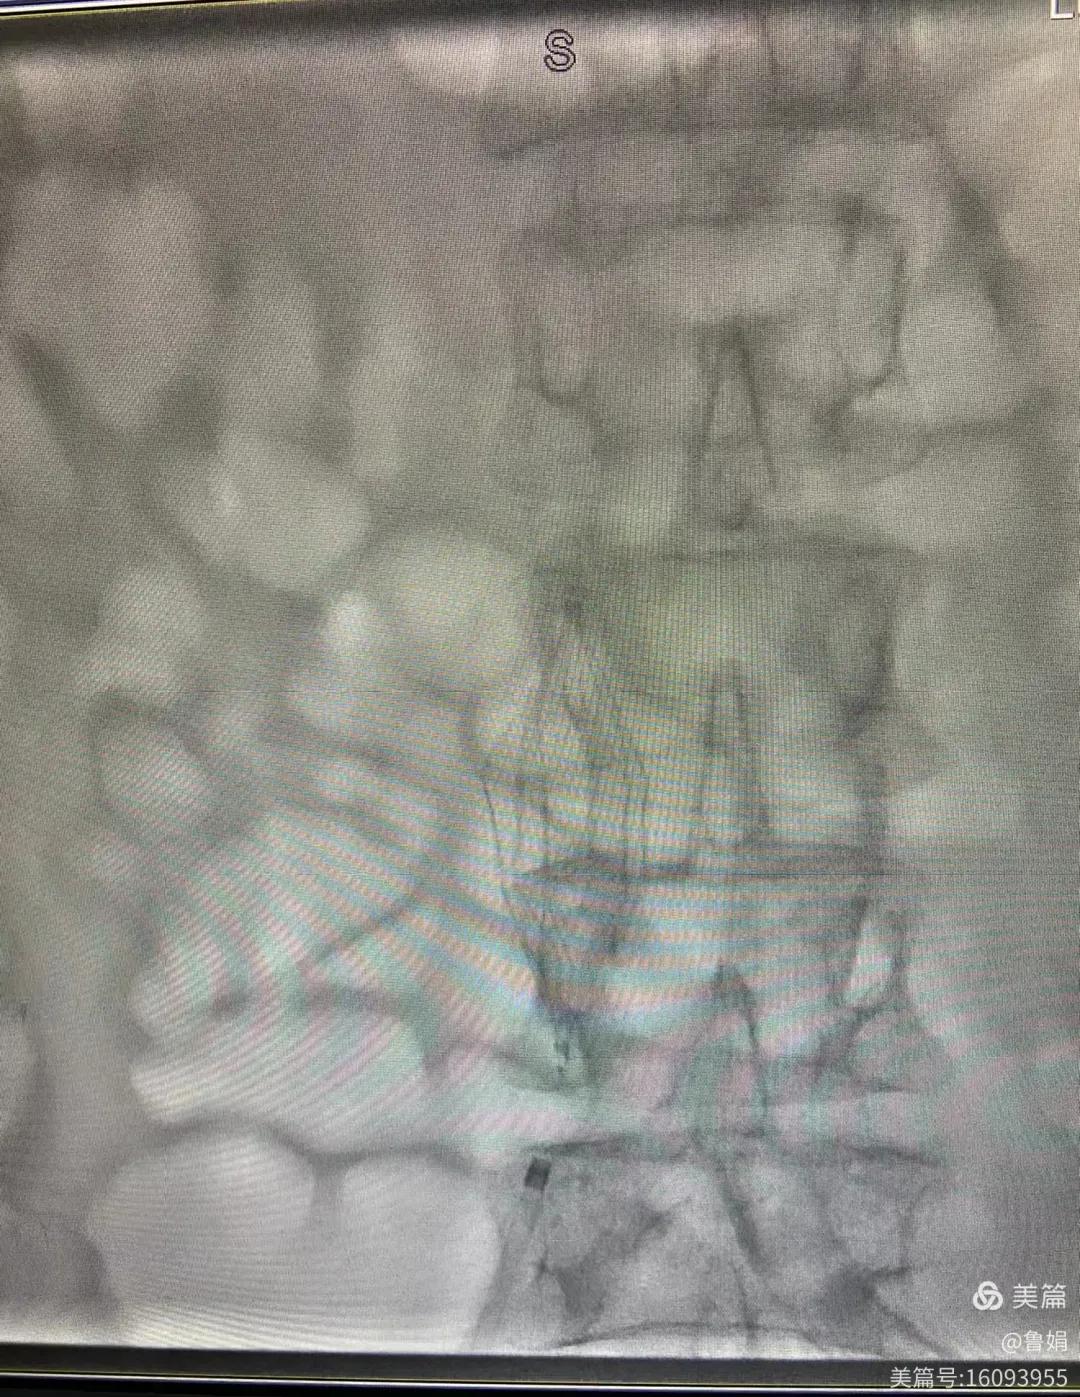

11月3日,漯河市中醫(yī)院血管外科副主任周創(chuàng)業(yè)與腦二科介入醫(yī)生孫亞中,兩位醫(yī)生為一位腦梗死伴下肢深靜脈血栓形成患者成功開展下腔靜脈濾器置入術(shù)。

圖片術(shù)后濾器順利植入

經(jīng)認真查看患者病例,探討患者病情及術(shù)中潛在風險因素,多科會診后急診為患者開展介入手術(shù),術(shù)中周創(chuàng)業(yè)副主任、孫亞中副主任中醫(yī)師二人通力合作,手術(shù)順利,病人術(shù)中出血少,生命體征平穩(wěn),現(xiàn)在腦二科病房繼續(xù)對癥治療。(介入中心:魯娟)